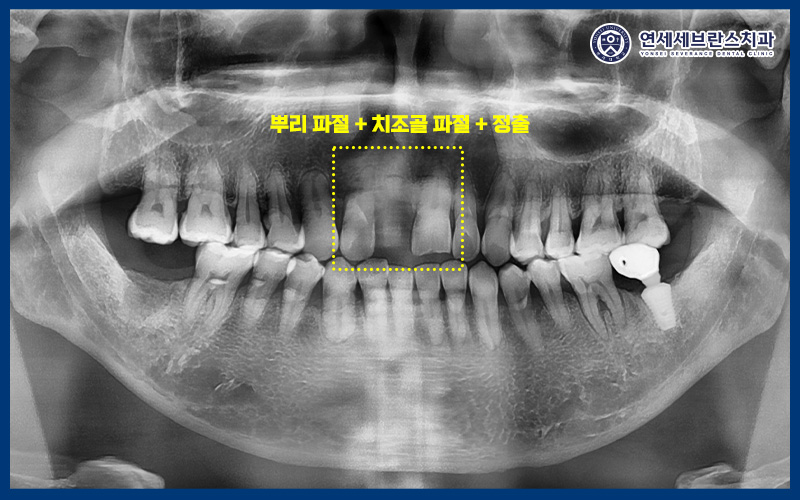

육안으로 확인 시 앞니가 부러져서

뿌리만 남아있던 상황이었습니다.

그리고 부러진 치아의 옆 치아는

많이 흔들리는 상황이고,

환자분께서 아래로

내려온 것 같다고 하셨습니다.

또한 CT를 촬영하여 확인해 보니,

왼쪽 위 치아는 치조골 골절을

관찰할 수 있었습니다.